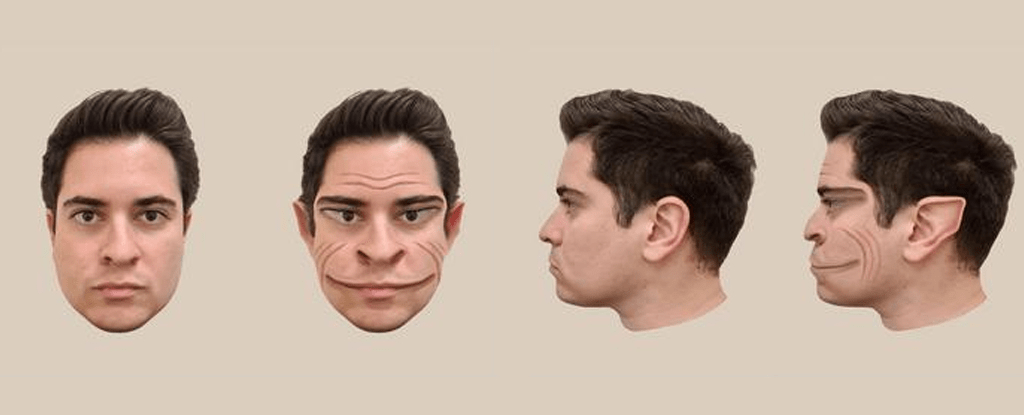

58 yaşında ABD’li bir erkek, dünyayı çoğumuzdan farklı bir şekilde görüyor. Bu fark insan yüzünü algılayışından kaynaklanıyor çünkü o, yüzleri insan yüzü olarak değil, bir yaratık olarak görüyor. Buna prosopometamorfopsi ya da kısaca PMO deniyor. Bu adam Dartmouth College’deki deneylere katılmadan önceki iki buçuk yılını çevresindeki yüzlerde delikler oluştuğunu, yanaklarda, alınlarda ve çenelerde buruşukluklar belirdiğini, gözlerin ve ağızların gerildiğini kulakların elf kulağına dönüştüğünü görmek zorunda kaldı. İlk başta rahatsız edici bir durum olsa da adam, zihninin dayattığı bu maskelere zaman içinde alıştı. Sonuçta dehşet hissi yaratsa da bunlar gerçek iblisler değildi ya.

Ama dikkat edilmesi gereken bir nokta var: Bu adam bu duruma nasıl geldi? Hayatının tamamını böyle geçirmemişti. Belki bipolar bozukluktan ya da travma sonrası stres bozukluğundan kaynaklanıyordu bu durum. Ya da 40’lı yaşlarının başında geçirdiği ciddi kafa travmasının bir sonucuydu. Psikologlar konunun üzerine eğildiklerinde deneğin PMO’yu hiç de tipik olmayan bir şekilde deneyimlediğini fark ettiler. Normalde diğer PMO’lu hastalar hem insan yüzünü hem de fotoğraflarını çarpıtılmış halleriyle görürken denek sadece gerçek hayattaki yüzleri çarpıtılmış olarak görüyordu. Fotoğraflarla ilgili herhangi bir sorunu yoktu.

Böylelikle psikologlar bir odadaki gönüllülerin fotoğraflarını deneğe göstererek hastanın bakışındaki farklılığını gözlemleyebildi. İşte Lancet’te yayınlanan çalışmada ortaya çıkan sonuç şöyle:

Hastanın algıladığı şekliyle erkek yüzündeki çarpıklıkların algılanış şekli bilgisayarda böyle oluşturulmuş. Fotoğraf: The Lancet

Bu arada çalışmaya konu olan kişinin hastalığının hipokampüsünün sol üst kısmında görülen bir cm’lik küçük bir lezyonun sorumlu olabileceği düşünülüyor.